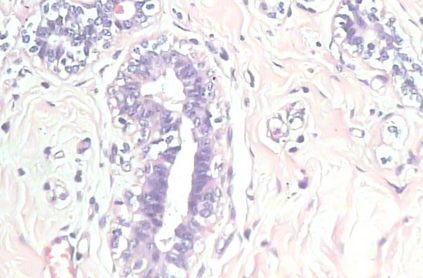

Background: Breast cancer has the highest prevalence in women globally. The classification and diagnosis of breast cancer and its histopathological images have always been a hot spot of clinical concern. In Computer-Aided Diagnosis (CAD), traditional classification models mostly use a single network to extract features, which has significant limitations. On the other hand, many networks are trained and optimized on patient-level datasets, ignoring the application of lower-level data labels. Method: This paper proposes a deep ensemble model based on image-level labels for the binary classification of benign and malignant lesions of breast histopathological images. First, the BreakHis dataset is randomly divided into a training, validation and test set. Then, data augmentation techniques are used to balance the number of benign and malignant samples. Thirdly, considering the performance of transfer learning and the complementarity between each network, VGG-16, Xception, Resnet-50, DenseNet-201 are selected as the base classifiers. Result: In the ensemble network model with accuracy as the weight, the image-level binary classification achieves an accuracy of $98.90\%$. In order to verify the capabilities of our method, the latest Transformer and Multilayer Perception (MLP) models have been experimentally compared on the same dataset. Our model wins with a $5\%-20\%$ advantage, emphasizing the ensemble model's far-reaching significance in classification tasks. Conclusion: This research focuses on improving the model's classification performance with an ensemble algorithm. Transfer learning plays an essential role in small datasets, improving training speed and accuracy. Our model has outperformed many existing approaches in accuracy, providing a method for the field of auxiliary medical diagnosis.